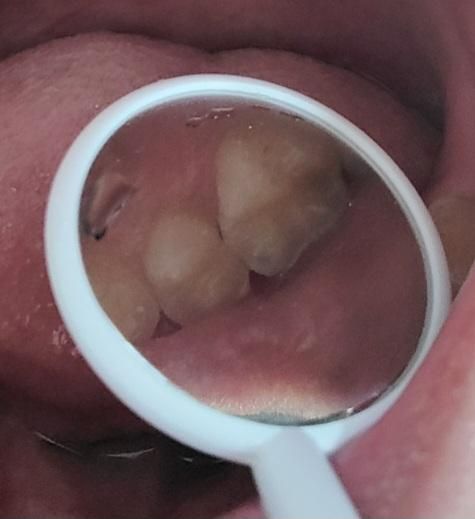

소구치와 대구치 사이가 까맣게 보여요.충치일까요?

제가 양치하고 치아를 살펴보니 소구치와 대구치 사이가 까맣게 보였습니다.

하지만 그 치아들은 9월에 레진치료를 받았고 10월에 충치확인을 위해 병원갔을 때도 별다른 이야기가 없었습니다. 하지만 그때 전체로 찍은 사진만 보셔서 조금 불안합니다.

• 2번 째 사진